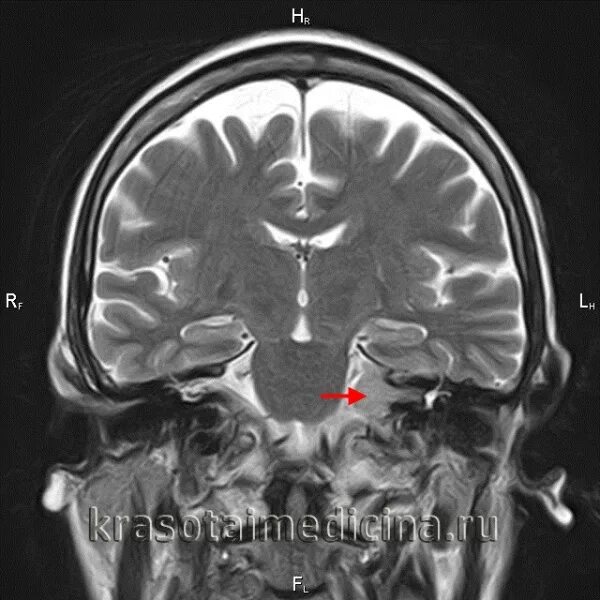

Мрт головного мозга мосто мозжечкового угла